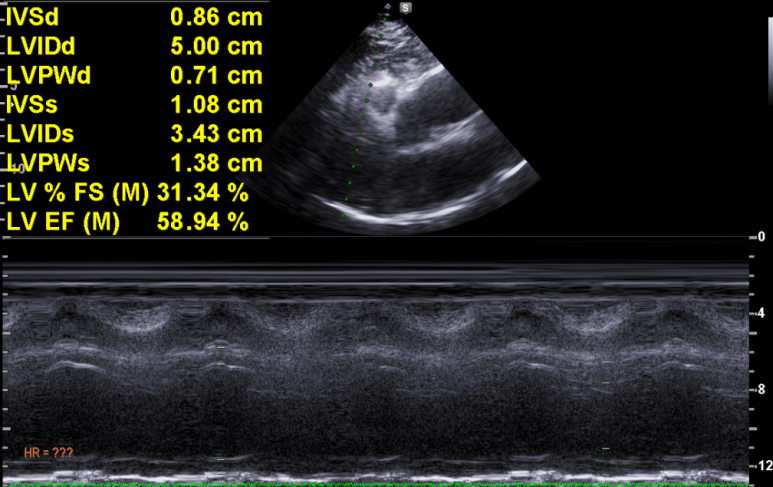

심실벽이나 심실의 비대/확장은 없으며

수축기 기능은 정상

G1의 이완기 장애